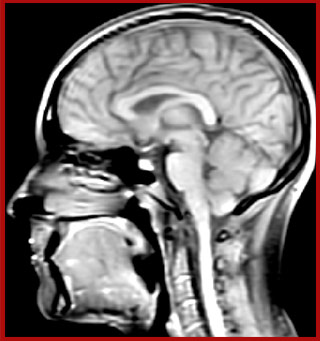

T1 - weighted

Myelin water imaging - T1 weighted

Myelin water imaging (echo 1)

Myelin water imaging with SENSE

Myelin water imaging with Compressed SENSE

T1 - Weighted, Myelin Water Fraction Superimposed

MWI Spinal cord coverage

Spinal cord coverage

MWI Smaller, more isotropic voxels

Smaller, more isotropic voxels

MWI Excellent detail in quantitative maps

Excellent detail in quantitative maps

Images courtesy of Adam Dvorak, Department of Physics and Astronomy, University of British Columbia

20%

Myelin water fraction

0%